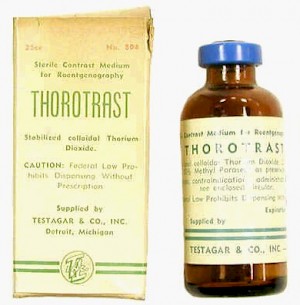

Thorotrast und Umbrathor sind die Handelsnamen für ein 1929 in den Markt eingeführtes Röntgenkontrastmittel, auf der Basis einer stabilisierten kolloidalen 25%igen Suspension von Thoriumdioxid.

Es wurde bis zu seinem Verbot Mitte der 1950er Jahre vor allem als Kontrastmittel für die Angiographie verwendet.

Meist wurde das Kontrastmittel in Mengen von ca. 20 ml unverdünnt intravenös oder intraarteriell injiziert.